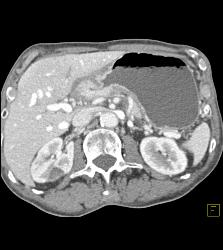

Antral Carcinoma